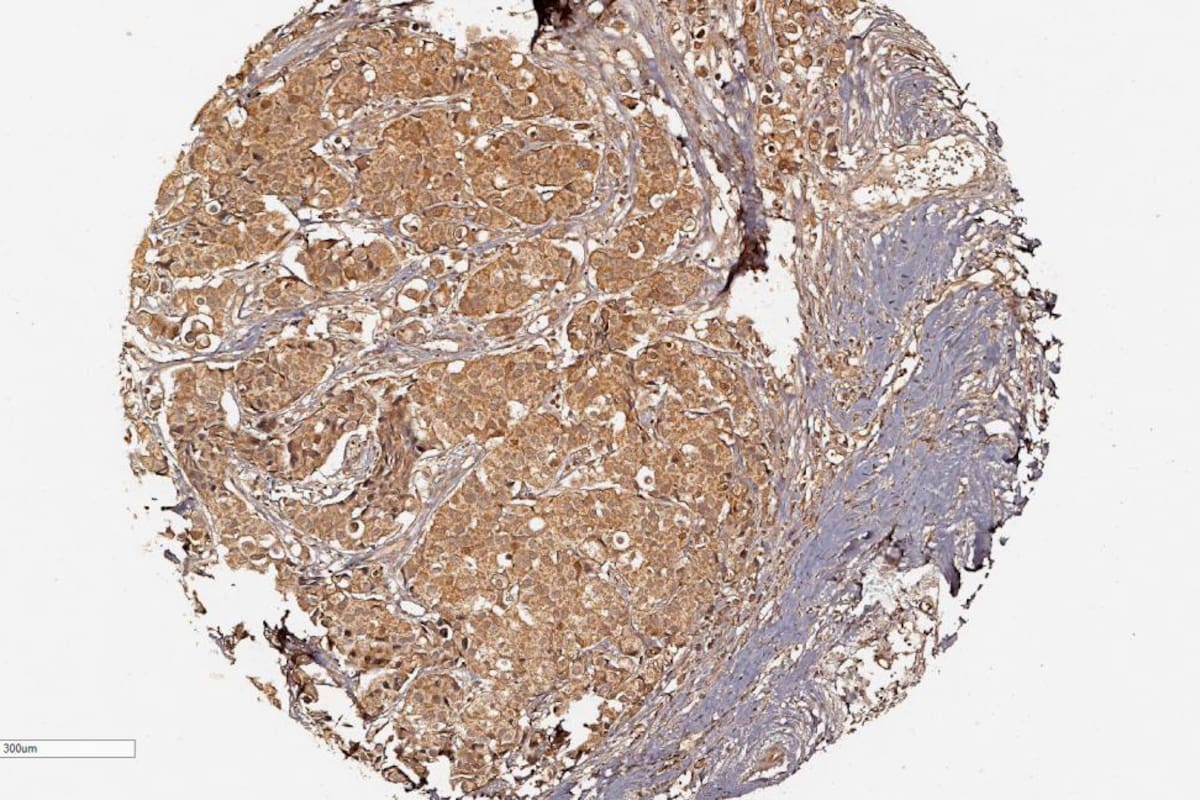

Los investigadores ya habían desvelado previamente que hay una serie de tumores de mama que presentan niveles altos de una proteína denominada Aurora A, implicada en la división celular y, por tanto, en la multiplicación del cáncer, explica a EFE Cadiñanos, director científico de la Fundación Centro Médico de Asturias.

La novedad de esta investigación es el descubrimiento de una agrupación de varias proteínas formadas por supresores tumorales, que disminuyen los niveles de Aurora A, y la capacidad de reproducción del cáncer.

En ese complejo proteico, los científicos identificaron una proteína en concreto, llamada PTEN, que es un potente supresor tumoral.